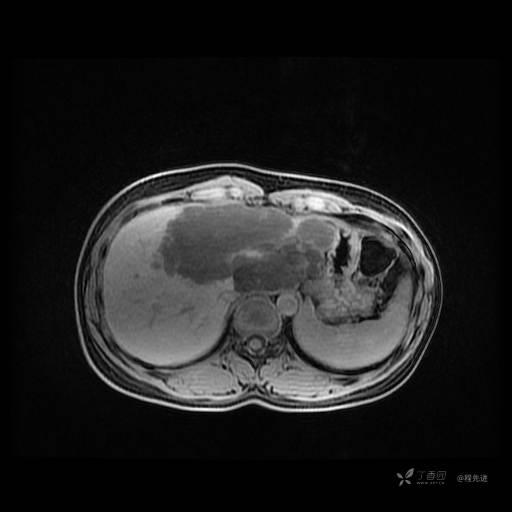

MR平扫+增强

每个序列一张图像(图像太多了,恕不一一发上来)